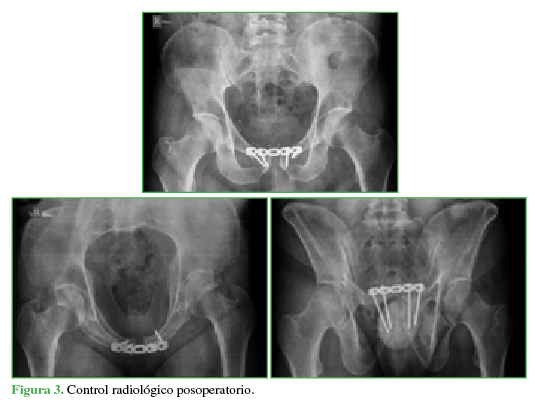

A las 24 h del episodio, la perfusión mejoró de forma sustancial. Al cuadro inicial se le agregó un marcado aumento del volumen del miembro como consecuencia de la estasis venosa y linfática. El paciente fue movilizado para el control radiológico posoperatorio (Figuras 3 y 4).